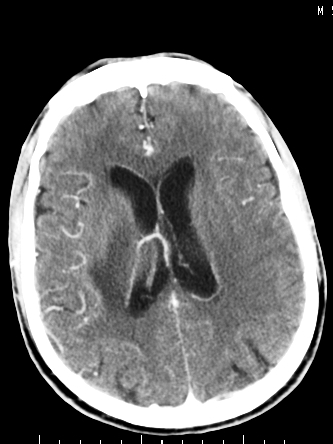

m/50,头昏头痛1月,近3天感觉左半肢体活动不利,自述半年前呈患肺tb,腰穿脑脊液未见特殊改变。现做头颅ct请大家会诊。

结核性脑膜炎,结核瘤,梗塞灶三症并存,提示颅内结核感染可能性大。

右侧基底节区缺血性脑梗塞.脑干区考虑结核.